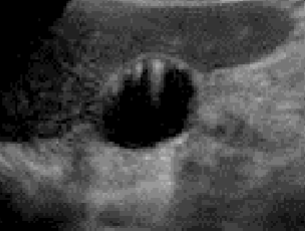

In the image, the gallbladder is located behind the bowel and is not visible. The black oval next to the bowel is this artifact mimicking the gallbladder.